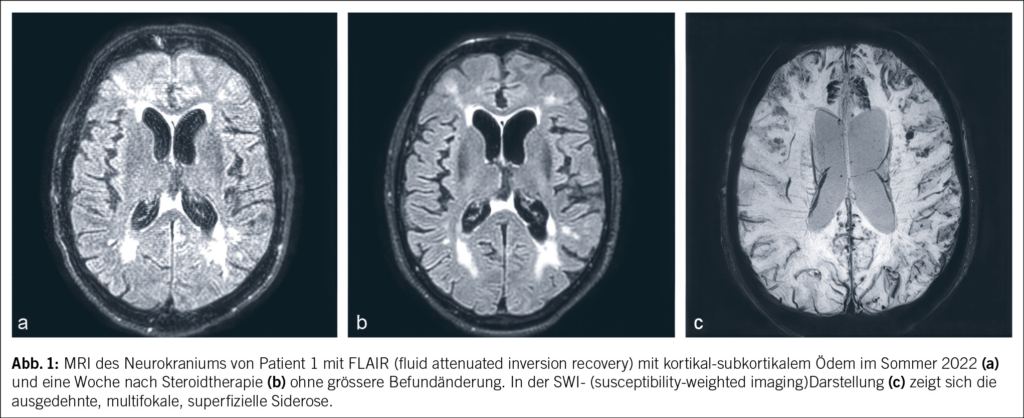

Ein 69-jähriger Mann litt seit März 2019 an unklaren rezidivierenden Dysästhesien und einer motorischen Beinschwäche links. Eine Magnetresonanztomographie (MRI) mit Angiographie des Neurokraniums zeigte keine Hinweise auf eine Durchblutungsstörung, Ischämie oder Raumforderung. Im Sommer 2019 erfolgte bei einer notfallmässigen Vorstellung aufgrund derselben Symptomatik eine Computertomographie (CT) mit Angiographie. Hier fanden sich weiterhin keine Hinweise auf eine Ischämie, jedoch kam eine mässige, am ehesten mikroangiopathische Leukenzephalopathie zur Darstellung. In der nachfolgenden Elektroenzephalographie (EEG) zeigte sich ein bitemporaler Herdbefund rechtsbetont mit Epilepsie-verdächtigen Einzelpotenzialen. Bei Verdacht auf rezidivierende fokal-epileptische Ereignisse wurde eine anfallssupprimierende Therapie mit Levetiracetam eingeleitet. Zunächst kam es zu keinen erneuten epileptischen Ereignissen. Neu wurde seitens der Ehefrau eine depressive Symptomatik beschrieben. Ein Montreal-Cognitive-Assessment(MoCA-) -Test im Januar 2020 fiel mit 18/30 Punkten pathologisch aus, sodass eine demenzielle Entwicklung vermutet wurde. Die empfohlene neuropsychologische Testung wurde nicht durchgeführt. Im Sommer 2020 wurde der Patient schliesslich bei raschem Fortschreiten der demenziellen Entwicklung und Allgemeinzustandsverschlechterung bei uns auf der neurologischen Station hospitalisiert. In der Lumbalpunktion fanden sich nun neben einer Schrankenstörung eine stark erhöhte Proteinzahl von 3600 mg/l (Normwert: 150–450 mg/l) und eine Erhöhung der Zellzahl von 21 mononukleären Zellen/μl (Normwert: < 4 Zellen/μl). Das Tau-Protein war mit 1266 pg/ml (Normwert: < 445 pg/ml) ebenfalls erhöht und das Beta-Amyloid-Protein mit 282 pg/ml (Normwert: > 375 pg/ml) erniedrigt. Das Phospho-Tau-Protein lag mit 35.5 pg/ml im Normalbereich (Normwert: < 61 g/ml). Diese Konstellation im Liquor mit erhöhtem Tau-Protein und erniedrigtem Beta-Amyloid-Protein kann sowohl für eine Demenzform wie Alzheimer aber auch eine inflammatorische cerebrale Amyloidangiopathie (Englisch: cerebral amyloid angiopathy related inflammation; CAA-RI) sprechen. Ein MRI des Neurokraniums mit Kontrastmittel zeigte eine ausgeprägte superfizielle Siderose, eine frische subarachnoidale Sickerblutung und ein Ödem frontal beidseits (Abb. 1). Diese Befunde waren passend für eine CAA-RI. Eine zentrale Manifestation einer systemischen Vaskulitis erschien bei negativen antinukleären Antikörpern (ANA) und antineutrophilen zytoplasmatischen Antikörpern (ANCA) unwahrscheinlich. Eine serologische Testung des sauren Gliafaserproteins (Englisch: glial fibrillary acidic protein; GFAP) und der Neurofilament-Leichtketten (NFL) erfolgte nicht. Insgesamt wurde nun die Verdachtsdiagnose einer inflammatorischen cerebralen Amyloidangiopathie gestellt. Eine Steroidstosstherapie mit Methylprednisolon intravenös 1 g/Tag über 5 Tage mit anschliessender Erhaltungsdosis mit Prednisolon von 1 mg/kg Körpergewicht wurde eingeleitet. Hierunter kam es zu keiner signifikanten klinischen Besserung. Im MRI des Neurokraniums mit Kontrastmittel nach 1 Woche konnte noch keine wesentliche Befundänderung dokumentiert werden. Die zuvor in der Liquorpunktion erhöhten Werte waren rückläufig (Proteinzahl 465 mg/l, 12 mononukleäre Zellen/μl).

Die Amyloidablagerungen sind bei einem Teil der Patienten mit einer Entzündung der Gefässwand vergesellschaftet, was schliesslich zu einem multifokalen Marklagerödem führt. Insgesamt zeigen diese Veränderungen im MRI ein typisches Bild, welche für die Diagnosestellung einer CAA-RI wesentlich sind. Die Veränderungen lassen sich vor allem in der FLAIR-Sequenz (fluid attenuated inversion recovery) und bei der SWI (Suszeptibilitätsgewichtete Bildgebung) feststellen (2, 3). Dazu gehören Mikroblutungen, eine kortikale superfizielle Siderose und eine asymmetrische fleckförmige oder konfluierende Leukenzephalopathie, welche den angrenzenden Kortex und das subkortikale Marklager miteinbeziehen können. Ebenfalls kann sich als Zeichen der entzündlichen Reaktion ein vasogenes Ödem in der ADC- (apparent diffusion coefficient) Wichtung präsentieren (2, 4, 5). Es wurden die sogenannten modifizierten Boston-Kriterien entwickelt, welche auf eine gute Sensitivität und Spezifität geprüft wurden (6) (Tab. 1) und bei der Diagnosesicherung helfen. Zusätzliche klinische Diagnosekriterien sind ein akuter/subakuter Symptombeginn, Alter über 55 Jahre, Symptome wie Kopfschmerzen, Wesensveränderungen, kognitive Defizite oder fokal neurologische Defizite oder epileptische Anfälle. Andere Ursachen (z. B. infektiös oder paraneoplastisch) müssen ausgeschlossen werden. Sind alle diese Kriterien erfüllt, gilt eine CAA-RI als wahrscheinlich. Zur definitiven Diagnosesicherung wird eine histologische Bestätigung im Rahmen einer Autopsie benötigt, wobei sich neben frischen und alten Ischämien und Einblutungen auch entzündliche, perivaskuläre Veränderungen ohne Gefässbeteiligung finden lassen. Hier kann eine Unterscheidung zur Beta-Amyloid-assoziierten Angiitis (ABRA) gemacht werden, welche ausgeprägtere vaskulitische Veränderungen und fibrinoide Gefässwandnekrosen zeigt. Diese erheblichen Zerstörungen des Hirnparenchyms direkt durch invasive zytotoxische T-Lymphozyten und indirekt durch vaskulitische oder begleitthrombotische Gefässverschlüsse bedingen eine stärkere Immunsuppression als bei der CAA-RI. Teils wird in der Literatur jedoch die ABRA synonym zur CAA-RI genannt. Ob eine Histologie zur Diagnosestellung einer CAA-RI immer zwingend ist, steht aktuell immer noch zur Diskussion. Eine genaue Diagnose hat jedoch teils therapeutische Konsequenzen. Vor allem bei fehlendem Therapieansprechen sollte eine Biopsie angestrebt werden.